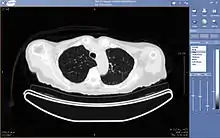

La téléradiologie consiste en la consultation et l'interprétation d'images radiologiques ou échographiques à distance.